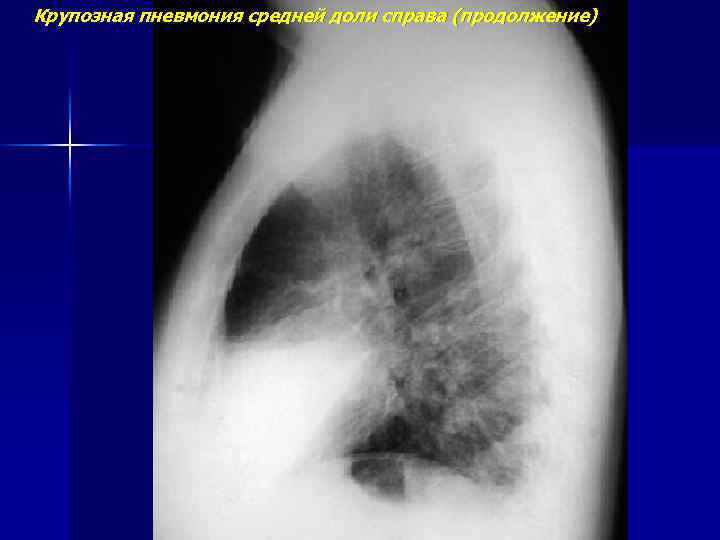

Крупозная пневмония средней доли справа

Крупозная пневмония средней доли справа (продолжение)